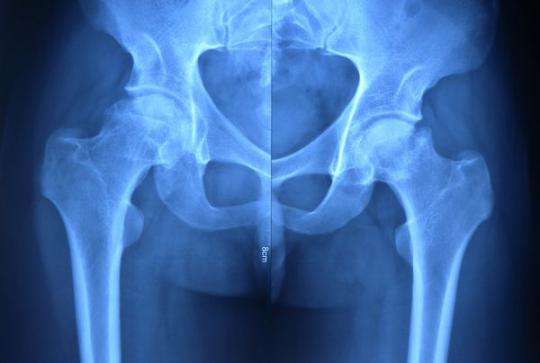

3.疾病累及肢带关节(髋关节、肩关节);

3.影像学:必要的应脊柱或骨盆(包括骶髂关节和髋关节)X线、MRI,对治疗方案决策和调整有重要指导作用;